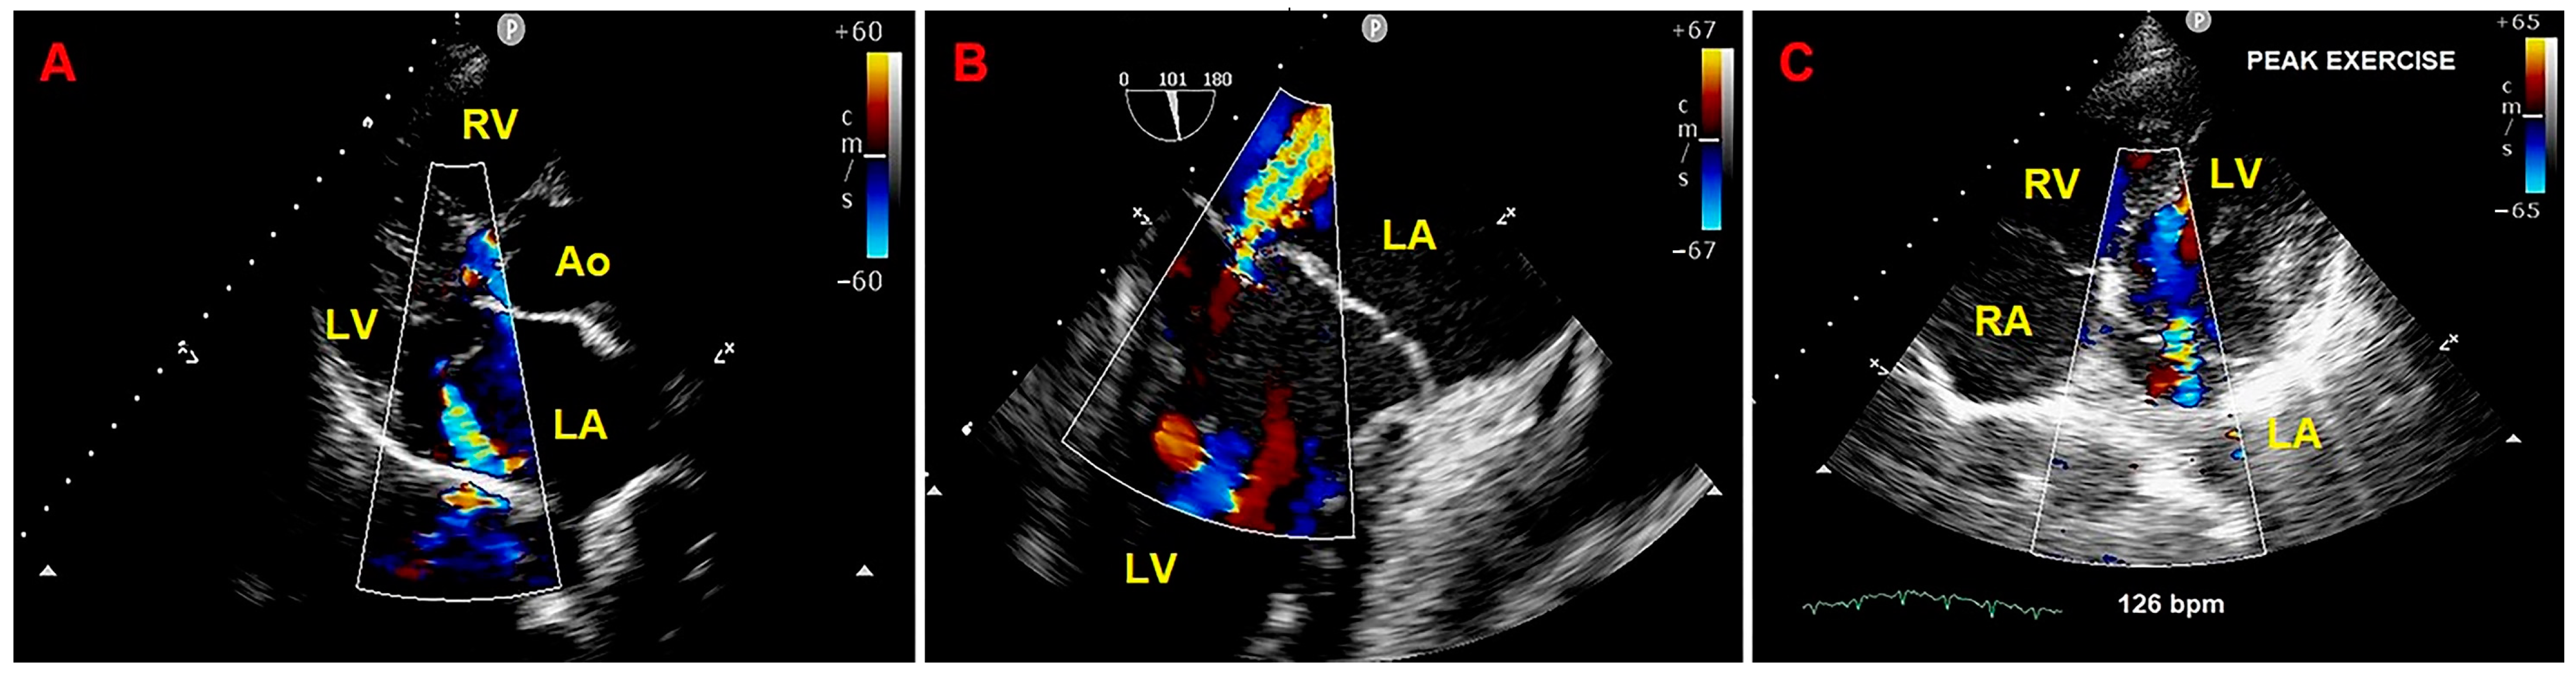

2. Clinical Case

3.2. The Role of Echocardiographic Techniques in MAD Assessment